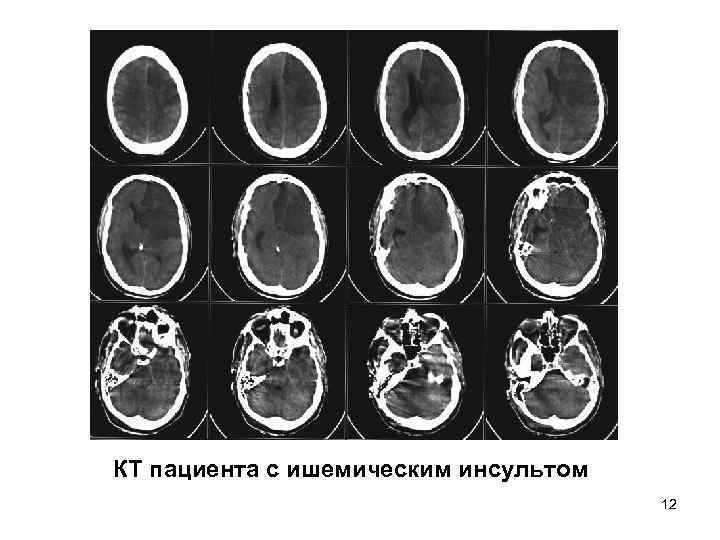

• КТ - 1. структурные аномалии • опухоль, гидроцефалия 2. воспалительные заболевания • абсцесс, энцефалит 3. сосудистые заболевания • кровоизлияние, острая субдуральная (эпидуральная) гематома, ишемический инсульт 4. перелом основания черепа 5. травма мозга 11

КТ пациента с ишемическим инсультом 12